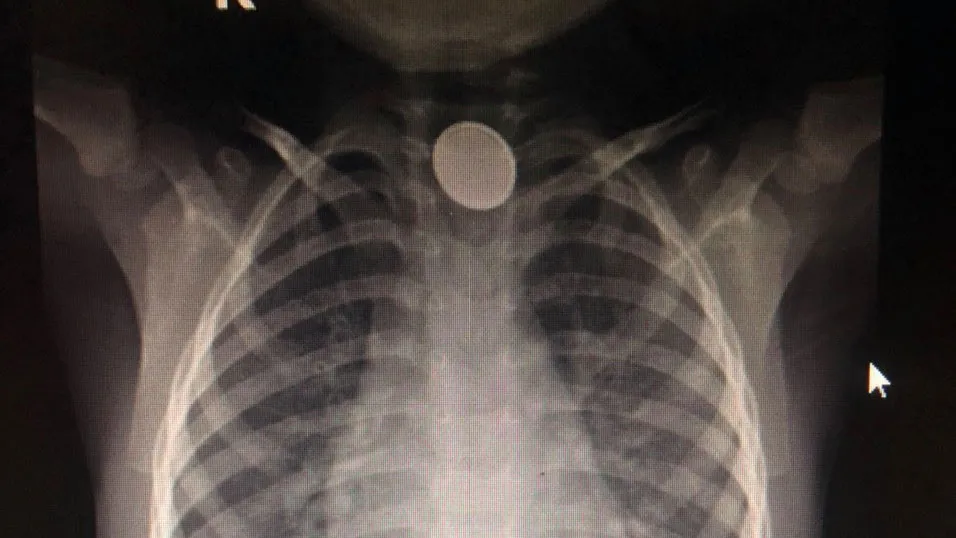

Hình ảnh chụp cho thấy chỗ 1/3 thực quản trên của bé có dị vật kim loại hình tròn. Bé được đưa vào phòng mổ để gây mê, nội soi gắp dị vật khẩn.

Theo bác sĩ Huỳnh Tấn Đạt, khoa Ngoại tổng hợp, Bệnh viện quận Thủ Đức, khi nội soi, phát hiện một vật hình tròn, dẹt như đồng xu chỗ thực quản trên. Các bác sĩ tiến hành gắp dị vật ra và phát hiện đó là một cục pin đang bị gỉ sét khiến hóa chất trong pin rò rỉ ra ngoài gây bỏng, viêm loét chỗ cuống họng và thực quản của bé.